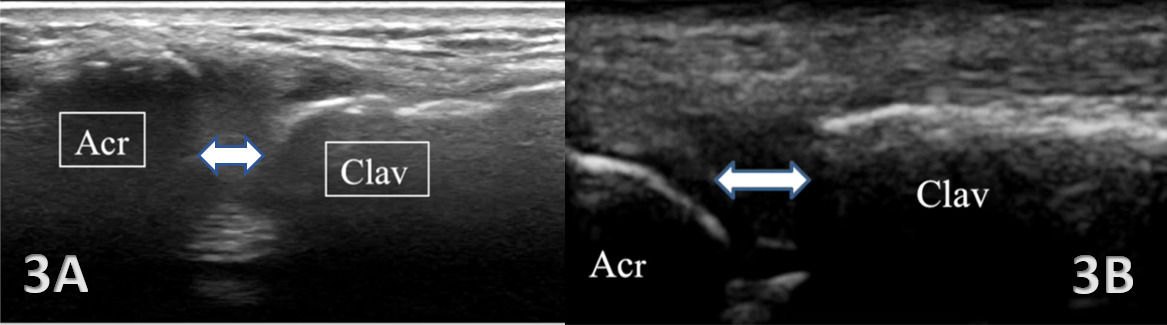

Sports physical therapists often deal with a range of musculoskeletal (MSK) issues, where accurate diagnosis and effective treatment are crucial for an athlete’s recovery and performance. The acromioclavicular joint (ACJ) plays a pivotal role in shoulder stability and movement, being the junction between the acromion process of the scapula and the clavicle. Given its importance, injuries to this joint, commonly resulting from falls, car accidents, or sports activities, can have significant repercussions. These injuries range from mild sprains, where ligaments are partially torn but the joint remains aligned, to severe dislocations with complete ligament tears and joint misalignment. Furthermore, repetitive use or wear and tear can lead to osteoarthritis of the ACJ, characterized by joint pain, stiffness, and swelling. Timely and accurate diagnosis is crucial for effective management. Traditional imaging techniques like radiographs often fall short in adequately assessing these injuries, particularly in visualizing soft tissues and dynamic joint function. MSK ultrasound has become increasingly popular for evaluating ACJ injuries, offering real-time, detailed imaging of soft tissue structures.

MSK ultrasound offers a non-invasive, cost-effective, and dynamic assessment of the ACJ. Its superiority in visualizing soft tissue structures, such as ligaments, articular cartilage, and the joint capsule, allows for a more nuanced diagnosis than what is achievable with radiographs. Its non-invasive nature also allows for repeated assessments, essential in monitoring the healing process or the progression of degenerative changes. This imaging modality is also beneficial for monitoring the healing process and guiding interventions such as injections.

In acute injury scenarios, MSK ultrasound effectively assesses the extent of ligament and soft tissue damage, aiding in the accurate classification or grading of the injury and facilitating appropriate treatment planning. In chronic conditions, MSK ultrasound aids in identifying degenerative joint changes due to repetitive use or aging. The ability to perform dynamic assessments with MSK ultrasound is particularly useful in evaluating joint stability and function. It also detects concomitant injuries like rotator cuff tears or fractures, often missed by radiographs. In chronic conditions, it helps identify structural changes within the joint due to repetitive stress or aging.